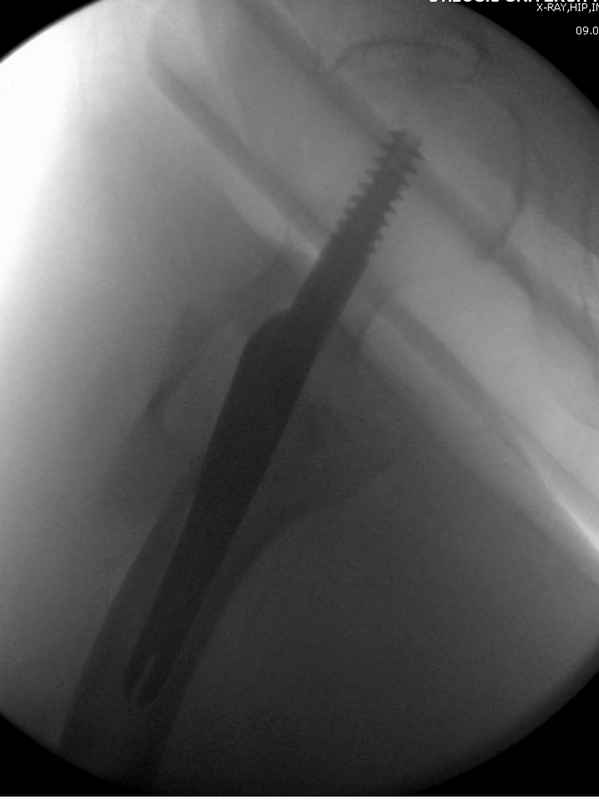

А вот к данным операциям без рентгена, как советует специалисты, я бы отнесся скептически, как раз здесь можно натворить много ошибок, например, от неправильной установки гвоздя мимо шейки до неудовлетворительной репозиции.

судя по картинкам с ЭОПа явно использовались приемы непрямой репозиции под его контролем, а так же интраоперационный ЭОП-контроль положения винтов, без такого контроля операция может ухудшить ситуацию (опять же учтите сроки) т.к. результат буде зависеть в большей степени от искусства хирурга, а не от технологии